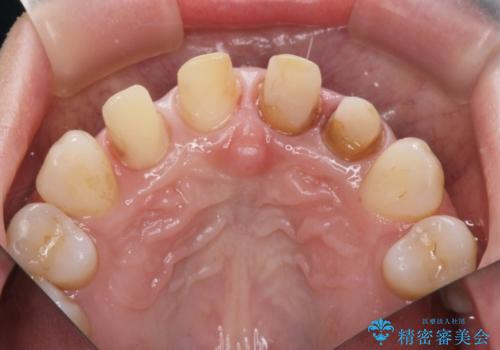

- 神経の死んでしまっている前歯の変色の改善を求めて来院されました。

根管治療をしたのち時間が経過して変色が目立つ歯と、レジン充填が複数箇所に及んでいる歯も同時にオールセラミック治療を行っていくこととなりました。

- 52.8万円(ジルコニアクラウン×4・仮歯×4)費用は治療当時の料金となります